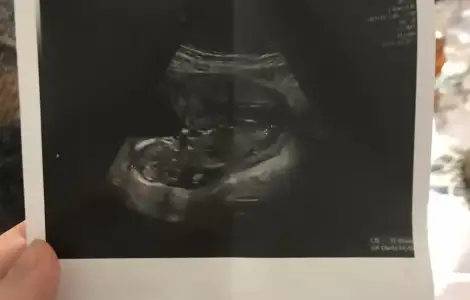

Bu iş sabır işi emek işi ama ultrasonda erkek dediklerinde gerçekten değmiş diyeceksiniz

Bu iş sabır işi emek işi ama ultrasonda erkek dediklerinde gerçekten değmiş diyeceksiniz